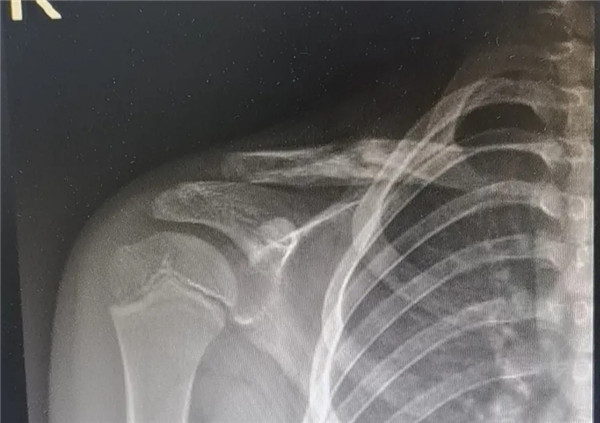

6月3日,在征得家屬同意,洋洋的身體符合手術(shù)指征后,洋洋接受了右鎖骨骨折切開復位內(nèi)固定術(shù),手術(shù)由應(yīng)文世主任主刀。術(shù)中可見右鎖骨呈粉碎性骨折,骨折端移位明顯。一個小時后,手術(shù)順利結(jié)束。術(shù)后,洋洋恢復良好,6月9日順利出院。一個月后,在來復查時,洋洋的媽媽帶來了一面錦旗送予應(yīng)文世主任及手外科周小君副主任,以感謝他們的高超技術(shù)及優(yōu)質(zhì)服務(wù)。

復位后